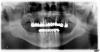

HotDog3_14 Опубликовано 31 марта, 2011 Поделиться Опубликовано 31 марта, 2011 Доброго здоровья , клыки я бы все же оставил. Они в более или менее хорошем состоянии, стоят в кости. а вобласти малярров резорбции костной ткани с обножением фуркации, поэтому вердикт однозначный - удалять. Ссылка на комментарий